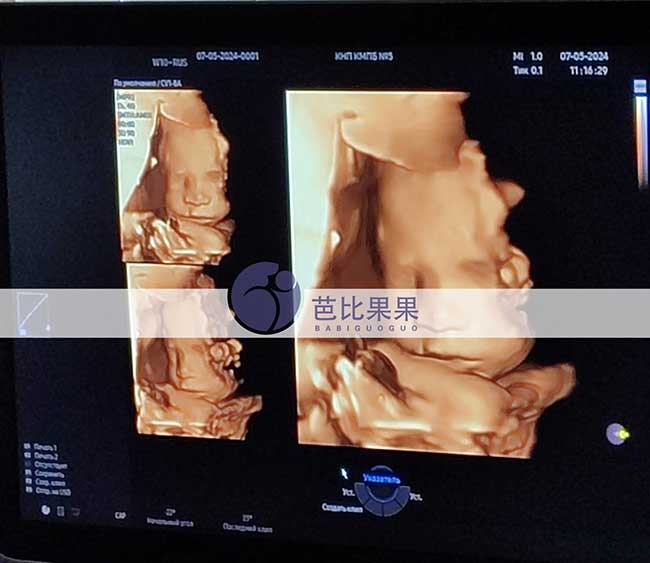

L女士家一如既往美丽的乌克兰试管妈妈来做四维检查

L女士家的乌克兰试管妈妈来做四维检查,还是一如既往的美丽,胎宝宝发育一切正常,8月就要和爸爸妈妈见面啦